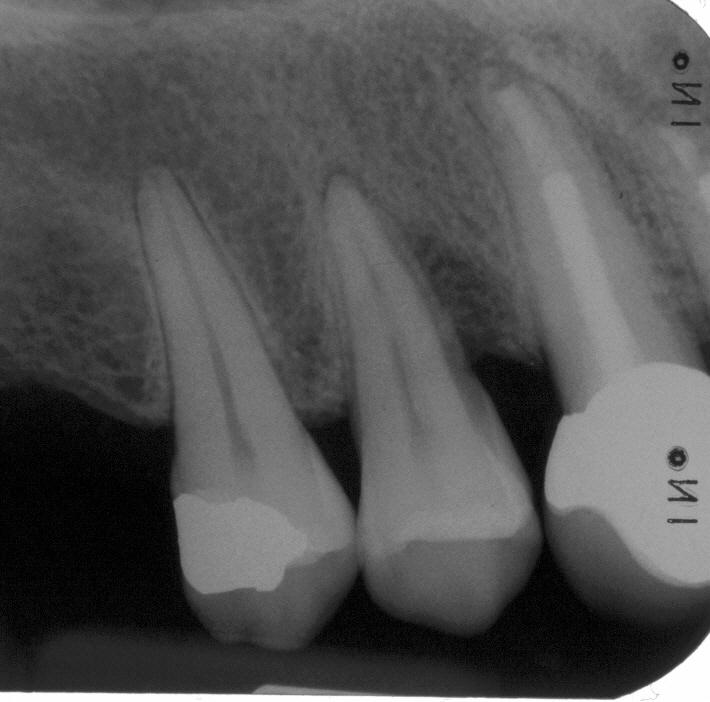

Langzeitkontrolle im Oktober 2003 mit röntgenologisch unauffälligem Parodontalspalt physiologischer Breite. Eine Wurzelspitzenresektion, die dann auch konsquenterweise am 12 hätte durchgeführt werden müssen, hätte die Zähne unnötigerweise geschwächt und wäre mit einer fraglichen Prognose verbunden gewesen

Langzeitkontrolle nach 16 Jahren in 2012 mit unauffälligem PA-Spalt physiologischer Breite